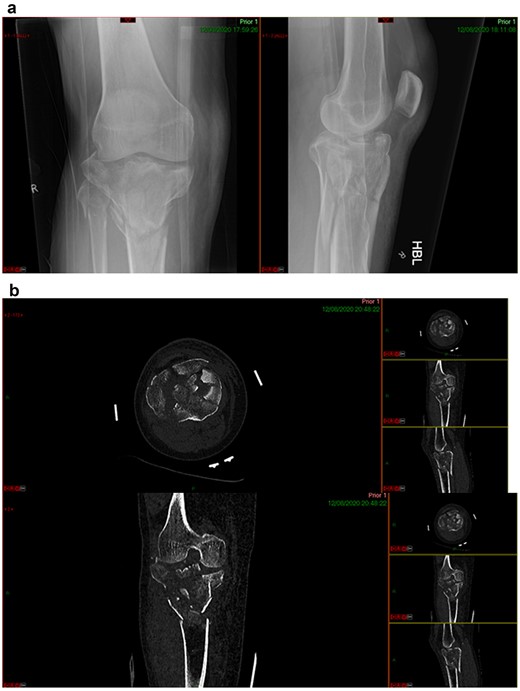

CASE 1

A 68-year-old gentleman who was diagnosed with a Schatzker type VI fracture having fallen 3 m from a ladder (Figs 1 and 2). The injury was closed and neurovascularly intact. The patient was monitored for signs of compartment syndrome. He rapidly developed significant fracture blisters that persisted for over 2 weeks despite regular dressing care. He was deemed too high risk for acute operative intervention because of a high risk of wound complications. Following a multidisciplinary team discussion, he was managed in a cast then a knee brace, mobilising non weight bearing for 12 weeks, at which point the fracture was seen to be healing in a valgus malalignment. The patient was allowed to partially weight bear and received physiotherapy. He was reviewed regularly until fracture had united (Fig. 3). At 8 months post-injury, the patient underwent total knee arthroplasty utilizing a Depuy Synthes (Warsaw, In) PFC Sigma TC3 tibial metaphyseal sleeve and stem, and femoral component without sleeve or stem (Fig. 4). The patient was reviewed post-operatively in clinic at 6 months, the wound had fully healed and the range of motion was 0°–120°. The patient’s pain was significantly reduced, and they were independently mobile. They were kept under annual review and seen at 5 years post-operatively with an Oxford Knee score of 35; the patient used no walking aids and was pain free at rest or during normal walking, with the radiograph demonstrating good osseointegration. The latest follow-up at 8 years revealed no radiographical change in implant (Fig. 5).